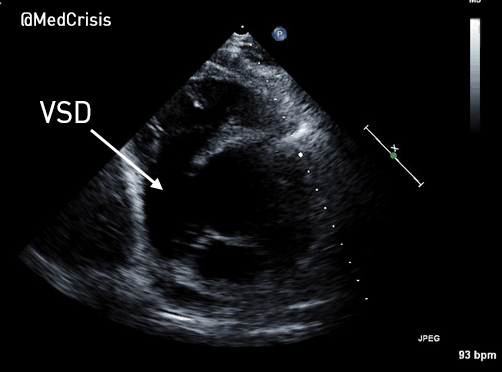

Parasternal short axis: There is a large ventriculo-septal defect in the infero-septal LV. The right ventricle is severely impaired.

The LV function is hyperdynamic. The infero-basal septum is tethered near the mitral and tricuspid valves but highly mobile, creating a large VSD. The right ventricular free wall appears to bulge out and the RV is almost akinetic.